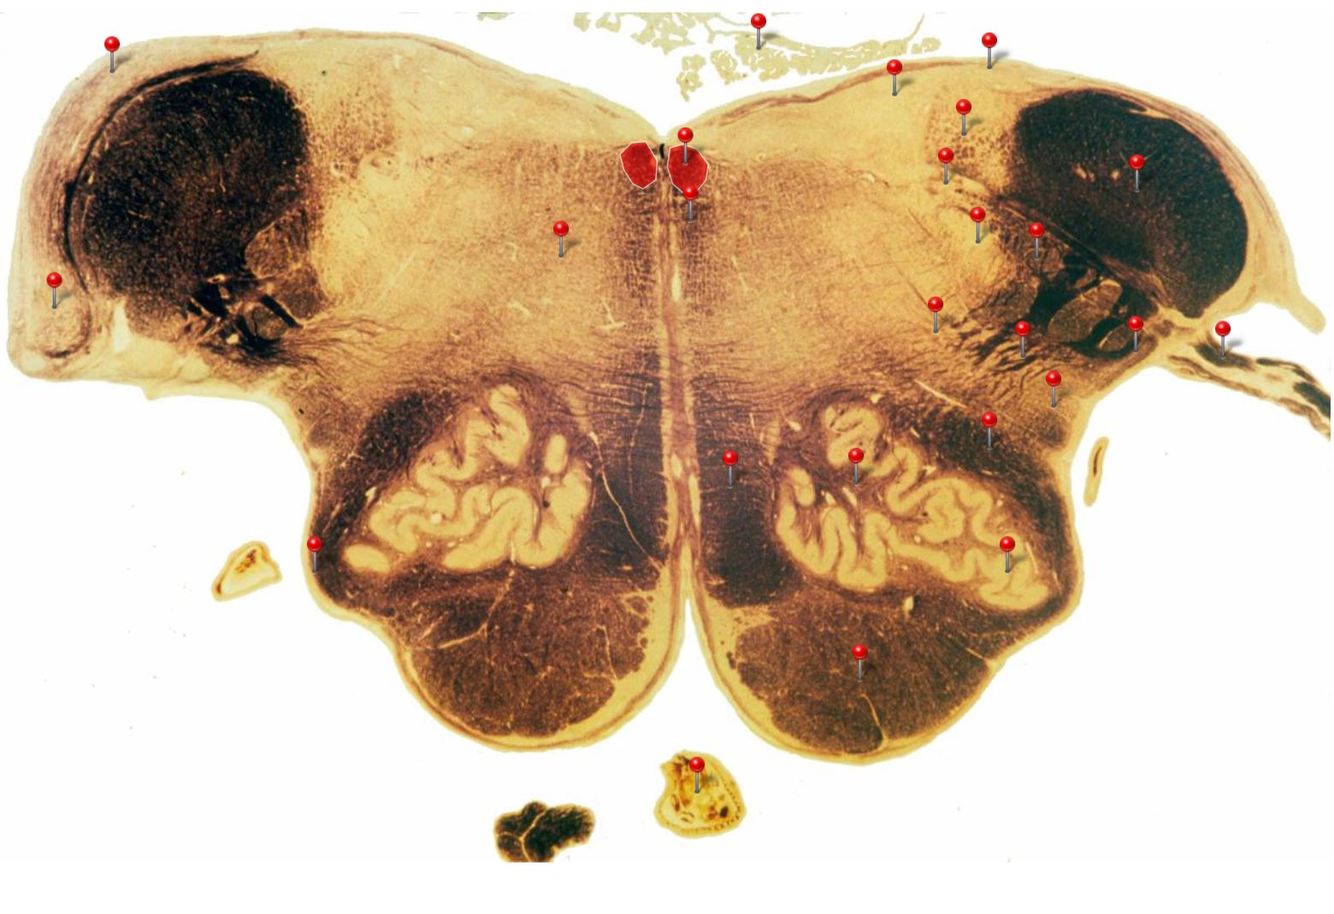

Caudal Midbrain

Transmits auditory info from the inferior colliculus to the medial geniculate nucleus of the thalamus

Edinger Westphal Nucleus

Oculomotor Nerve (CN III)

Supplies extraocular muscles (4 out of the 6; levator palpebrae of upper eyelid, ciliary and sphincter pupillae of the eye)

Corticospinal Tract

Controls precision and speed of skilled movements involving the distal muscles of the contralateral limbs, particularly those of the hands and fingers

5

Q

A

Rubrospinal Tract

Assists in the control of movements of the hands and fingers

Oculomotor Nucleus

Neurons give rise to GSE fibres of the oculomotor nerve (CN III) which supply extraocular muscles (4 out of the 6, as well as some fibres of the levator palpebrae superioris m.)

Spinothalamic Tract

Transmits pain and temperature sensations from the spinal cord to the thalamus

Superior Colliculus

Important relay centre for visual reflexes

Periaqueductal Gray (PAG)

Important centre in modulating pain transmission in the spinal cord, particularly in conditions of extreme stress (indirectly through connections with reticular formation)

Medial Longitudinal Fasciculus

Pathway through which eye movements are coordinated with changes in head position